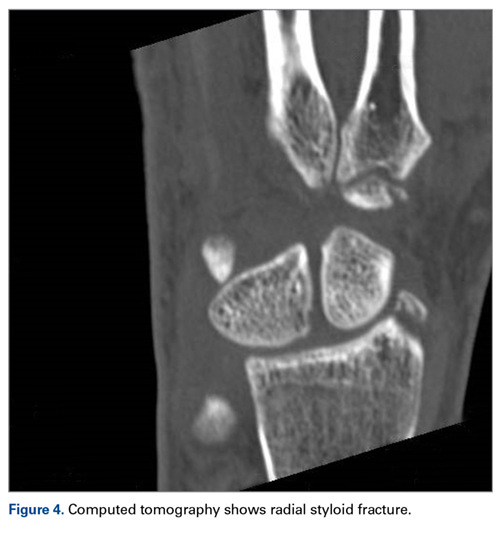

Later, however, the hand surgery team evaluated the radiograph as well as computed tomography (CT) scans and found a translunate, transradial, transtriquetral, transtrapezoid perilunate dislocation of the wrist with multiple metacarpal neck fractures ( Figures 1-5 ).The next day, with the patient under general anesthesia, an attempt to reduce the perilunate dislocation by manipulation was unsuccessful. Open reduction and internal fixation (ORIF) were performed through a dorsal approach; the perilunate dislocation was reduced and stabilized with lunocapitate 1.2-mm Kirschner wire (K-wire). The scapholunate and lunotriquetral ligaments were found to be intact, and the significantly displaced triquetral fracture was treated with internal fixation involving 2 minifragment screws ( Figure 6 ).

Perilunate injuries are classified as lesser arc injuries (purely ligamentous) or greater arc injuries (osseoligamentous). Greater arc injuries involve fracture of one or more carpal bones with associated ligamentous injuries. 3 The greater or lesser arc injuries described by Mayfield and colleagues 2 imply a specific pattern of force transmission with axial loading in a dorsiflexed and ulnar-deviated wrist with intercarpal supination. Graham 4 introduced a concept of inferior arc injury with the forces passing through the radiocarpal joint with fracture of the radial styloid or juxta-articular margin. Similarly, lunate fracture in perilunate dislocations was explained by Bain and colleagues 5 in the translunate arc concept in which forces pass through the lunate bone. A study involving a literature review of translunate perilunate dislocations noted associated transradial, trans-scaphoid, transcapitate, and transtriquetral fractures in order of decreasing frequency. 6 To our knowledge, no case of translunate perilunate dislocation with multiple carpal and metacarpal fractures with radial styloid fracture has been reported in the literature.

Perilunate injuries have been missed in busy emergency departments and orthopedic practices. An estimated 25% of such injuries can be missed on initial presentation. 8 In the present case, fracture of the radial styloid provided a clue to possible more complex carpal injuries involving the scaphoid, lunate, or scapholunate ligament, as Graham 4 suggested with the concept of the “transverse pattern” of force transmission. In this case as well, the injury was initially missed, and its extent became evident only with CT. Therefore, emergency teams should have a very low threshold for suspecting and evaluating high-energy wrist injuries.